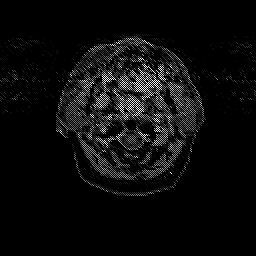

Glioma overlay -- Slice #0

[Home][Help][Clinical] Slice 0